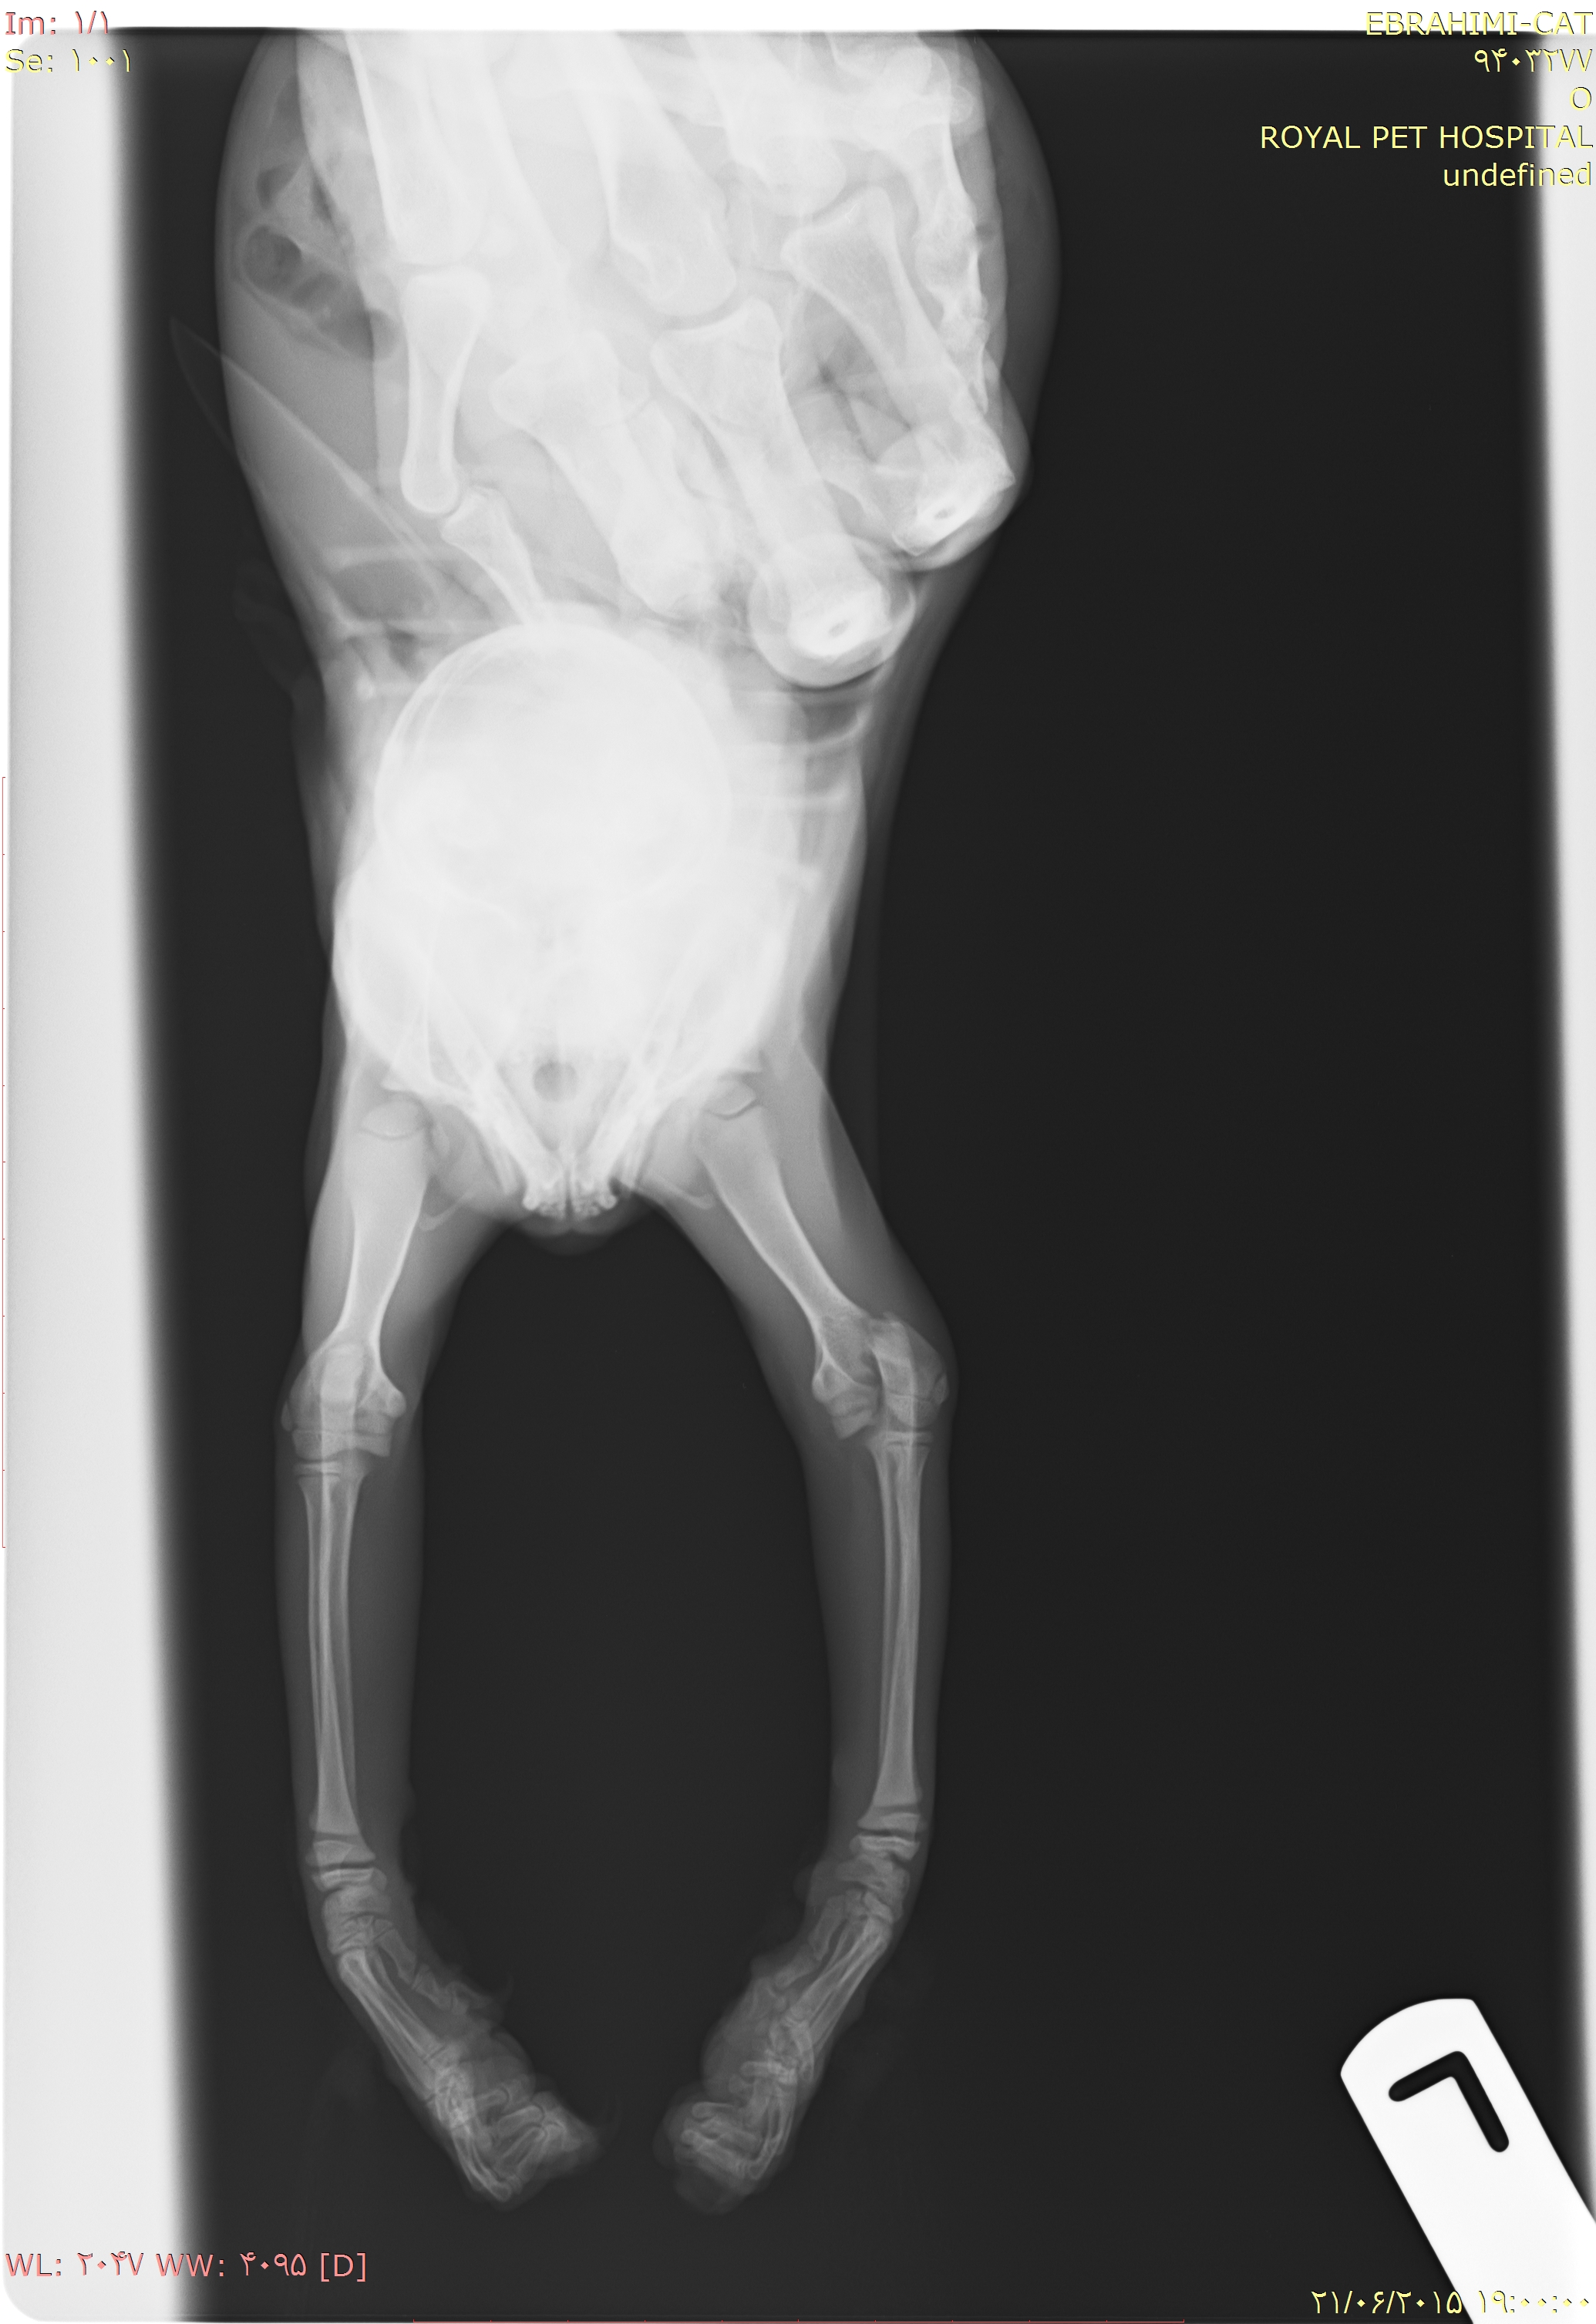

باسلام و احترام

گربه دوماه و نیمه ی من بعلت سقوط از ارتفاع دچار صدمه دیدگی شده.میخواستم نظرتون رو درمورد عکس هایی که ضمیمه میکنم بدونم.آیا نیاز به عمل جراحی هست یا خیر؟ باتشکر( این سوال 10 سال قبل مطرح شد و 10 سال قبل به این سوال پاسخ داده شده است. )